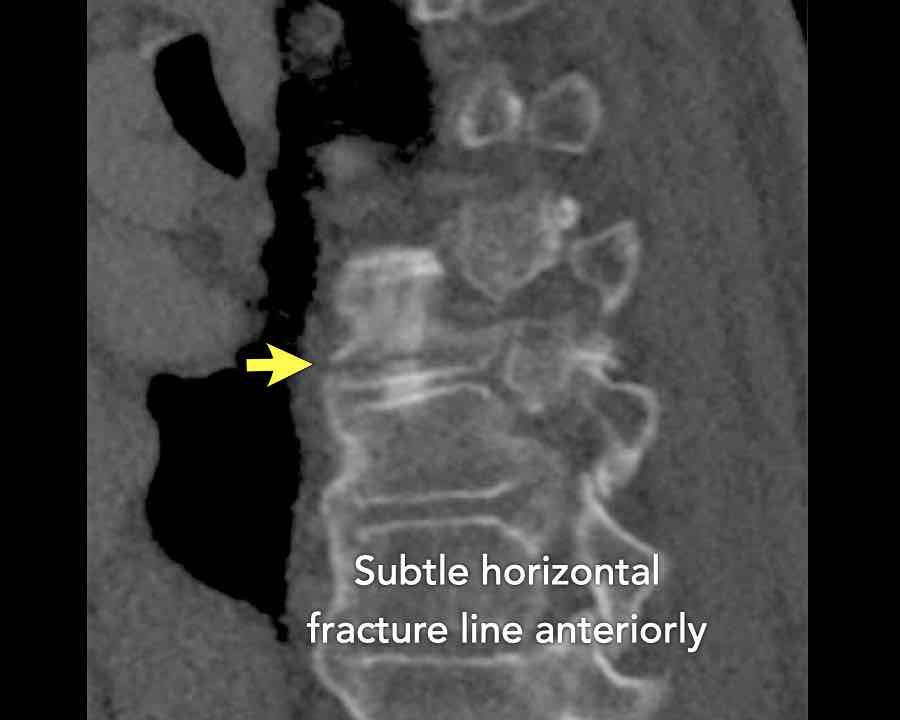

Scroll through images.

What are the findings?

Findings

- C injury? No.

- Signs of a rigid spine?

Yes, a B3 injury is very likely. - A subtle fracture on the anterior vertebral body.

Conclusion

Injury type B3.